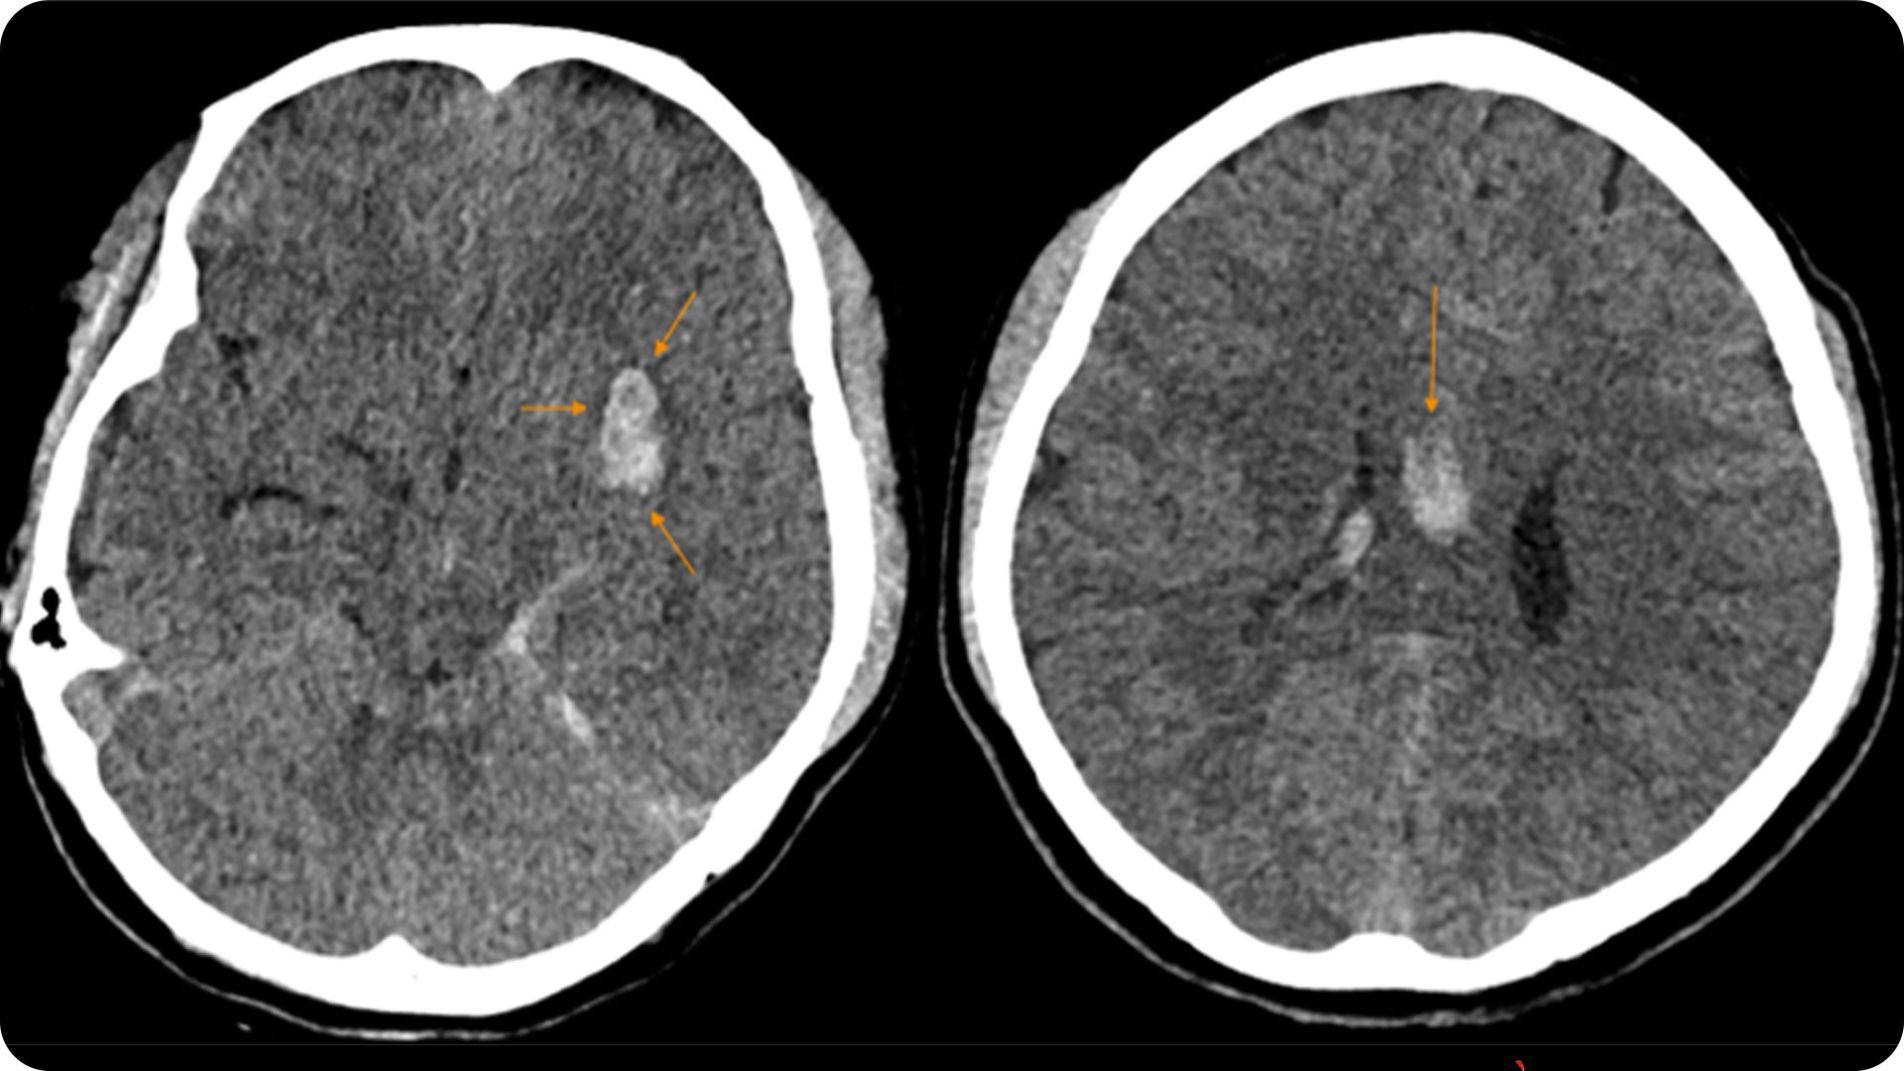

Hình ảnh CT scan não minh họa khối máu tụ trong xuất huyết não

- CT scan não không cản quang: phương pháp ưu tiên hàng đầu trong cấp cứu — cho kết quả nhanh, phát hiện khối máu tụ ngay trong vài phút đầu